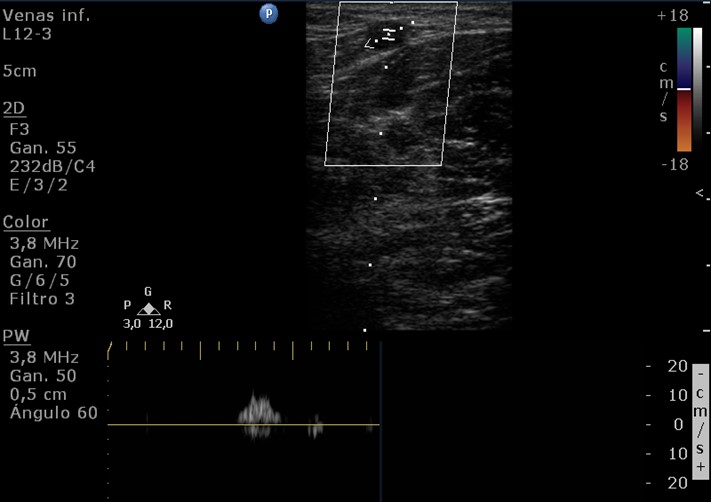

Sistema de venas perforantes. Son vasos de un diámetro que no debe superar los 3 mm. Atraviesan la aponeurosis muscular y comunican el sistema venoso superficial con el sistema venoso profundo, mediante un sistema valvular que en condiciones normales permite el drenaje de sangre en ese sentido. La forma de cono truncado, con el orifico externo menor que el interno favorece direccionar el flujo desde el sistema superficial al profundo (4) (Fig. 3 y Fig. 4).

Las venas perforantes se diferencian en: directas, que comunican el sistema venoso profundo con las venas safenas; e indirectas, que lo comunican con alguna vena tributaria. Cuando se invierte el flujo de la perforante por in-suficiencia venosa, se denominan “perforantes de fuga”, esta es una condición anormal, que requiere tratamiento, las perforantes de reentrada compensan a las de fuga, tienen dirección normal (4).